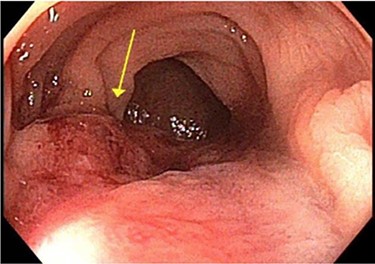

Surveillance colonoscopy in 2018 identified a fungating nonobstructing mass in the sigmoid colon (Fig. 1). Histology from a biopsy showed poorly differentiated carcinoma (Fig. 2). Given the history of breast cancer, further immunohistochemical staining was performed, which was positive for E-cadherin (Fig. 3), ER (Fig. 4), PR, GATA3 binding protein (GATA 3) (Fig. 5) and negative for Cytokeratin 20 (CK20) (Fig. 6). This confirmed metastatic invasive ductal carcinoma of breast. A positron emission tomography (PET) scan showed only the retroperitoneal mass involving the proximal sigmoid colon with no other evidence of metastatic disease (Fig. 7).

Histology slide of the biopsy with H&E staining showing poorly differentiated carcinoma.